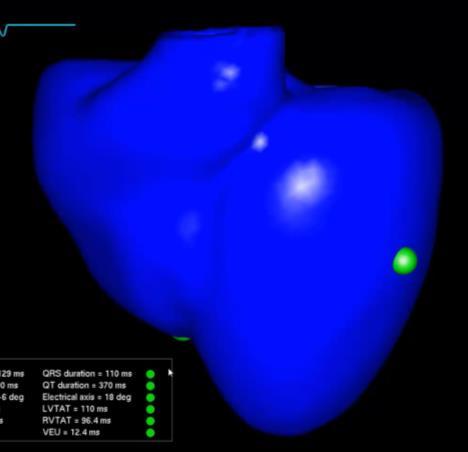

What if we could create a digital twin of the patient’s heart?

• Multiscale, Personalized Physiological Model of the patient’s heart

• Anatomy, Electrophysiology, Biomechanics (muscle contraction ), Circulation (ejection fraction, pressure dynamics)

• Mechanistic and statistical modeling

• Model is under our control

• Potential to test and prescribe best therapy for the patient – e.g., Cardiac Resynchronization Therapy

Ventricular Tachycardia Atrial Fibrillation Dyssynchrony – Heart Failure

Identify the ablation targets that will effectively terminate persistence AF? Identify the minimal ablation targets (catheter, RT) that will effectively terminate VT?

Cardiac radioablation –focus radiation using localization of VT exit

Anticipate the effects of CRT on patient’s cardiac function from preoperative data?